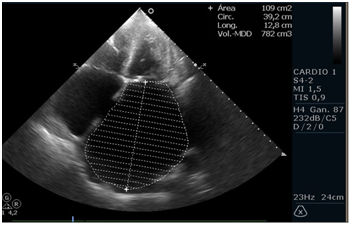

Patient of 75 years, height 165 cm and weight 72kg, with a history of mitral valve disease secondary to Rheumatic Fever. Percutaneous valvuloplasty was performed with balloon (Tecnica de Inoue) 6 years ago. Found in permanent atrial fibrillation(AF), NYHA functional class II, medicated with acenocoumarol, enalapril 10mg 2times/day, carvedilol 6.25mg 2times/day, spironolactone 25mg/day, furosemide 20mg/day and rosuvastatin 20mg/day. A Doppler echocardiogram is requested for dyspnea. It highlights the great biatrial dilatation to left predominance with moderate to severe mitral regurgitation, thickened mitral valve with characteristic stiffness (anterior valve in hockey stick), mitral stenosis moderated to severe by hemipresion time (THP) with an average of 10 beats (per to be found in atrial fibrillation rhythm) and systolic pressure in the pulmonary artery of 47mmHg. Left ventricular systolic function preserved. The left atrium measures 10.7cm in the anterior-posterior direction, an area in 4 chambers of 109 cm and an area in 2 chambers of 102cm2, obtaining a volume by the biplane method of 778ml (428ml/m2), remarking that currently the normal area by echocardiography is less than 34ml/m2.1 He presented with upper gastrointestinal bleeding with third episode of significant bleeding in 2 months that required blood transfusion due to gastric and duodenal ulceration. Mitral valve replacement is proposed with biological prosthesis, reduction of atrial volume, closure of left atrial appendage and isolation of pulmonary veins (Figure 1-3).

Figure 3 Apical echocardiographic view of two cameras with left atrial area measurement widely increased (103 cm2) and inferosuperior distance of 12.6 cm. Obtaining a volume of left atrium by biplanar method of 778 ml